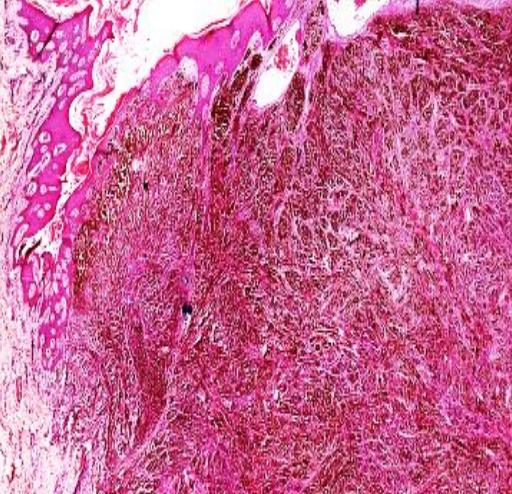

Mickulicz cell with foamy cytoplasm, lymphocytes, plasma cells and Russel bodies

Squamous cell carcinomoa

Nests of malignant epithelial cells infiltrating the dermis. The tumor masses are variable in size and shape,